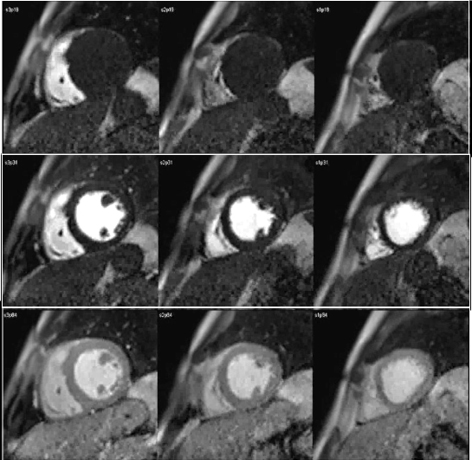

Perfusion defects in different territories can be detected in case of multivessel disease (Fig. 7) and, in patients with severe 3-vessel CAD, the perfusion study may show a global, intense, persistent defect which is readily recognizable (Fig. 8).

Fig. 7.Two-vessel perfusion defect. Stress perfusion defects at the anterior (white arrows) and inferior (black arrows) walls, not present at rest. Angiography (right panels) shows significant stenoses (white arrows) of the LAD (upper panel) and the right coronary artery (RCA) (lower panel).